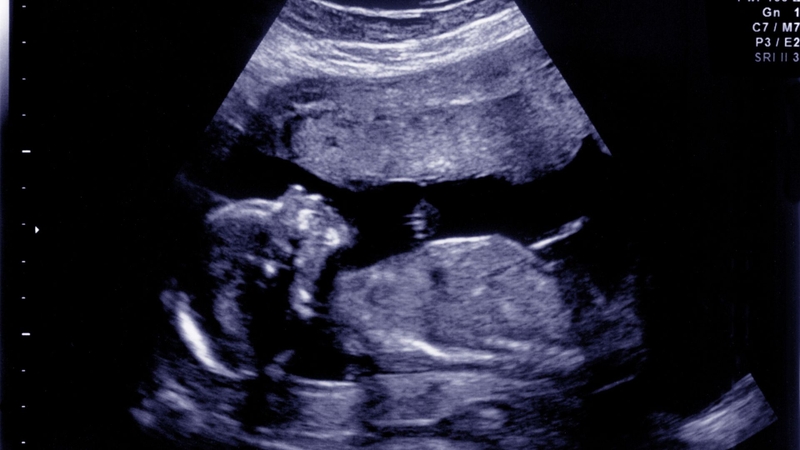

Ruột tăng âm ở thai nhi cần phải làm gì? 3

Hình ảnh ruột đôi khi có thể xuất hiện sáng hơn thực tế do cài đặt máy siêu âm